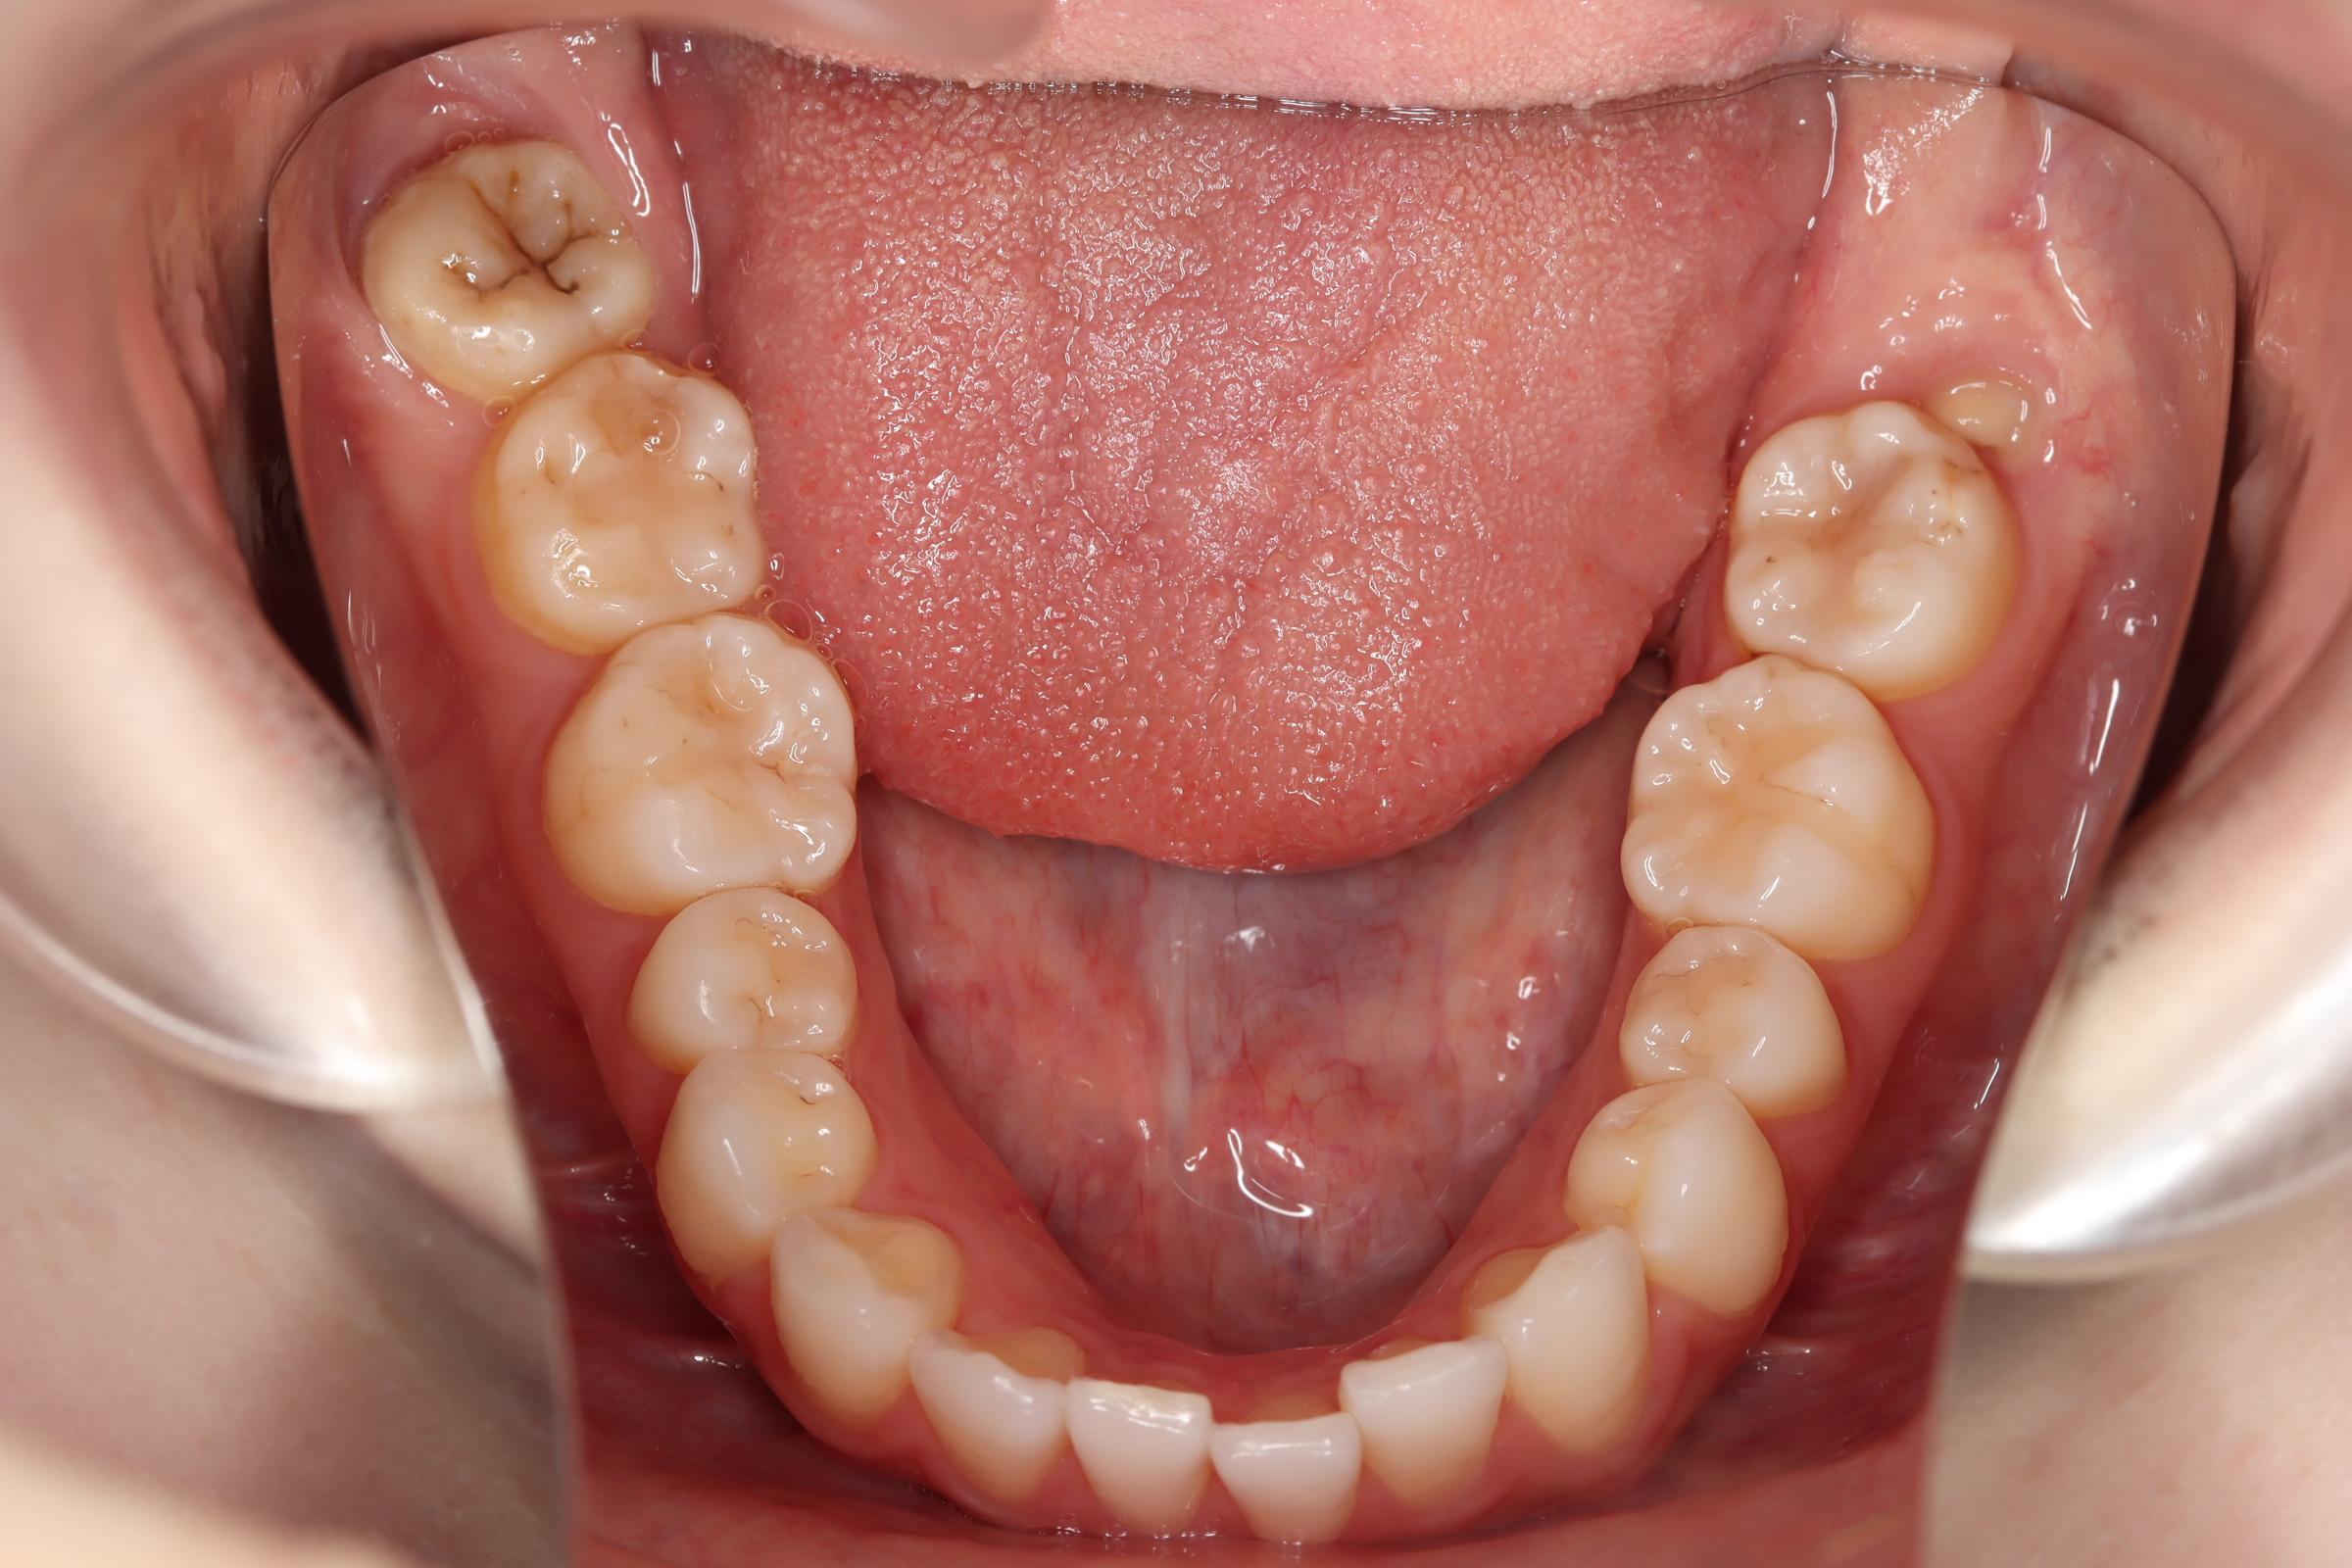

口腔内の変化

![]() | ![]() | ![]() |

| ↓ | ↓ | ↓ |

治療前後の解説

| 治療前 | 骨格的には受け口の患者さんですが、上顎前歯の唇側傾斜が大きく、患者さんとしては出っ歯だと思われていたパターンです。 元々口元の突出感はほとんどなかったため、歯を抜かずに上下顎ともに歯列を後方に移動させることにより主訴を改善させることとしました。 |

| 治療後 | 前歯から奥歯まで全体的に緊密な咬み合わせになっています。 治療前後のセファログラムのトレースの重ね合わせを比較すると、上下の歯列の後方移動ができ、それにより口元もよりすっきりしました。 また前歯の唇側傾斜も改善されています。 |